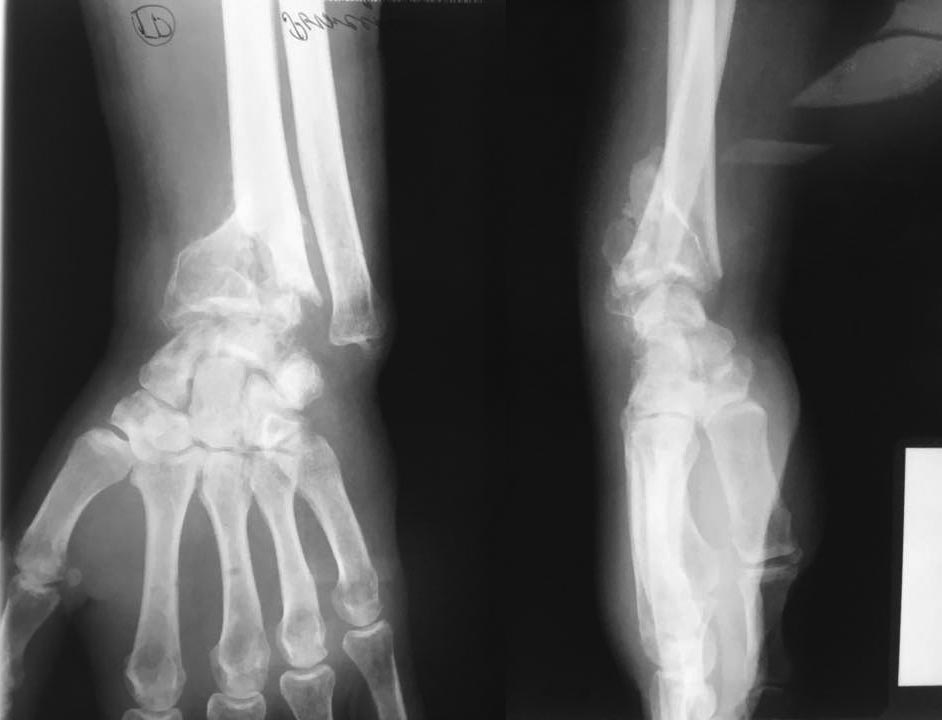

Дистальный луч

Добрый вечер, травма 5 мес назад, лечили гипсом в Ставропольском крае. Есть предложения?